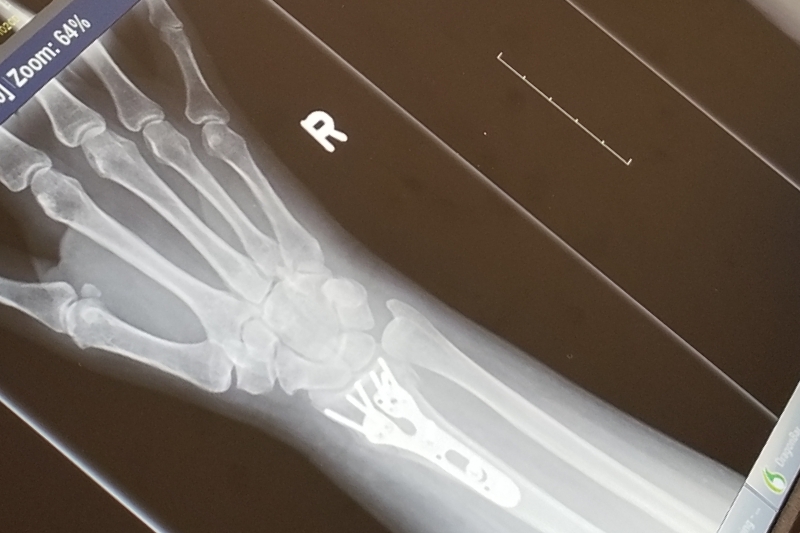

While I was in Houston working at the Alley Theatre I was hit by a pickup truck, breaking my right wrist. (So glad it was only that!) I'm now unable to work, because you kind of need two hands to do what I do, and have no money coming in right now to pay for all those wonderful day to day needs... like rent, food, phone... lawyer's fees... So, I'm asking for a bit of help until I get back on my... feet/ two hands. Help if you can, I'd really appreciate it!